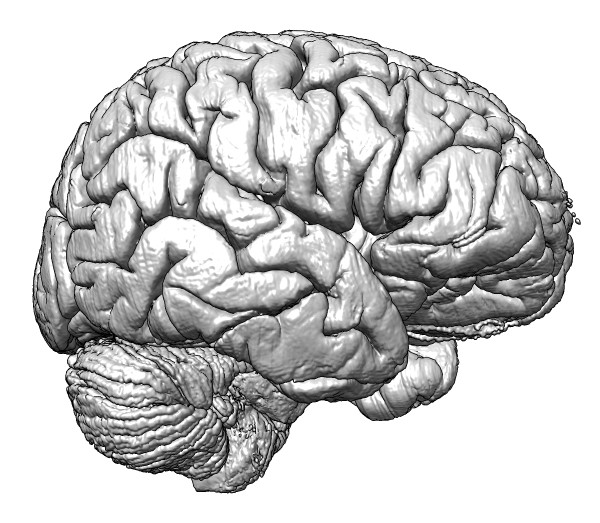

| Brain surface

- Show Big Brain 400 um volume surface rendered.

- Move around with space navigator and leap motion. Let everyone try.